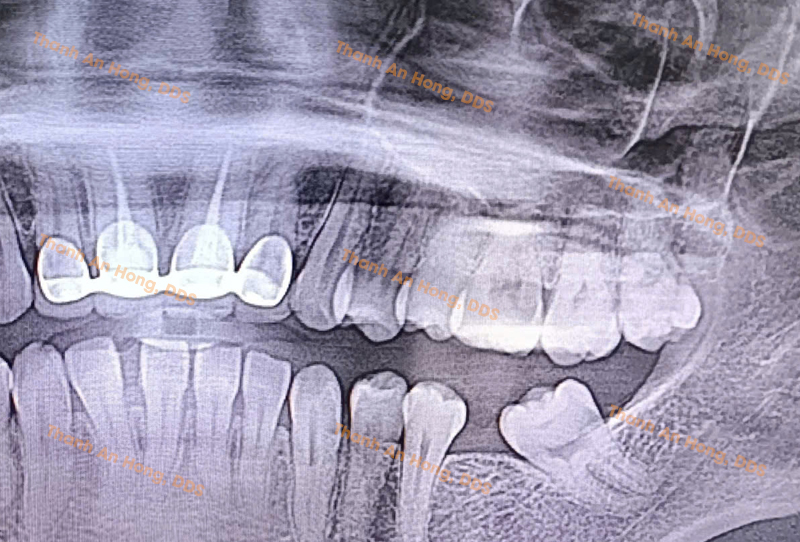

HÌNH ẢNH THỰC TẾ

Dì Gân Răng Cối Lớn Hàm Dưới